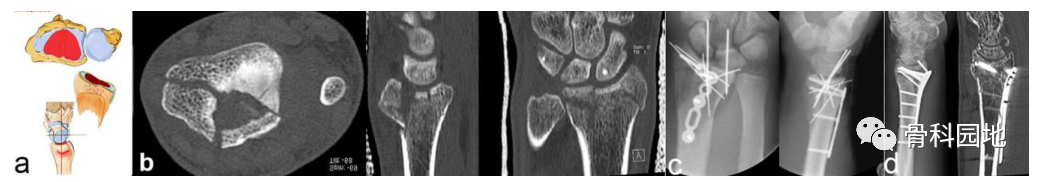

注:可以是大的或较小的边缘碎片。可能发生掌侧脱位,而背侧韧带保持完整 (a)。掌侧骨块:重要的尺桡韧带和尺腕韧带的起源 (b)。向掌侧脱位(c)。掌侧骨折从尺侧延伸到桡侧(d)。在 X 光平片上很容易忽略小的掌侧尺骨骨块,但轴位 CT 扫描容易显示该骨块 (e)

注:背侧脱位,背侧外部插入。手掌韧带断裂(a)。普通 X 射线显示背侧脱位的程度。然而,在 CT 扫描中,可以看到关节面的额外凹陷、S 状切迹的台阶和背键骨块 (b)。背侧骨块不一定是关键骨块。如左两个图像所示。尽管背侧脱位,但掌侧骨折块仍附着在掌侧韧带装置上,这个由骨韧带组成的掌侧关键骨折块需要特别注意,必须首先固定,如图所示(c)